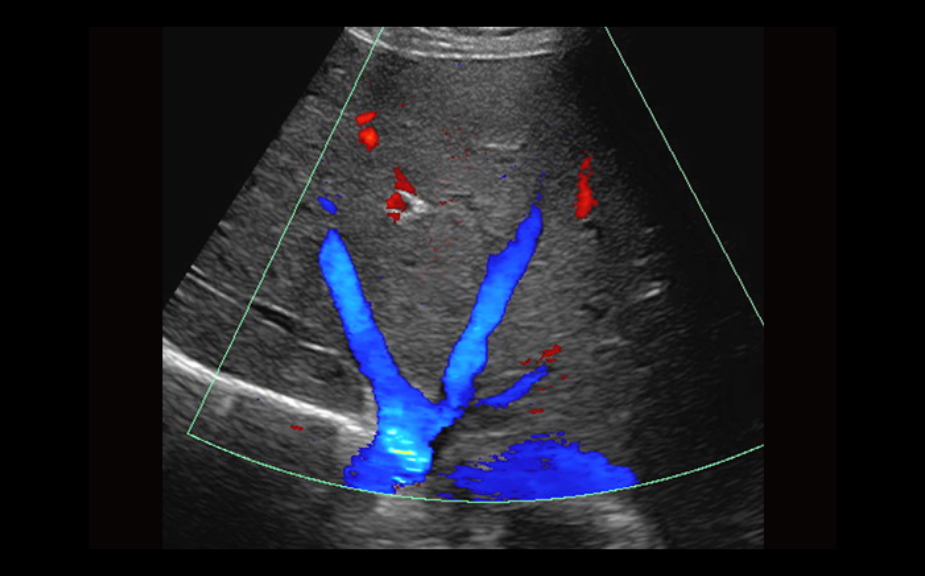

Equipped with patented, software based ZONE Sonography? Technology (ZST), the Z.One PRO provides optimally detailed B-mode and Doppler imaging for patients, regardless of body habitus, helping assure a reliable diagnosis.

Throughout a wide range of applications, the Z.One PRO is the ultrasound solution for your demanding clinical challenges.

- Unsurpassed image quality across all applications

The Z.One PRO is powered by ZONE Sonography Technology, an innovative and proprietary image formation architecture that acquires and processes acoustic data up to ten times faster than conventional beamforming methods.